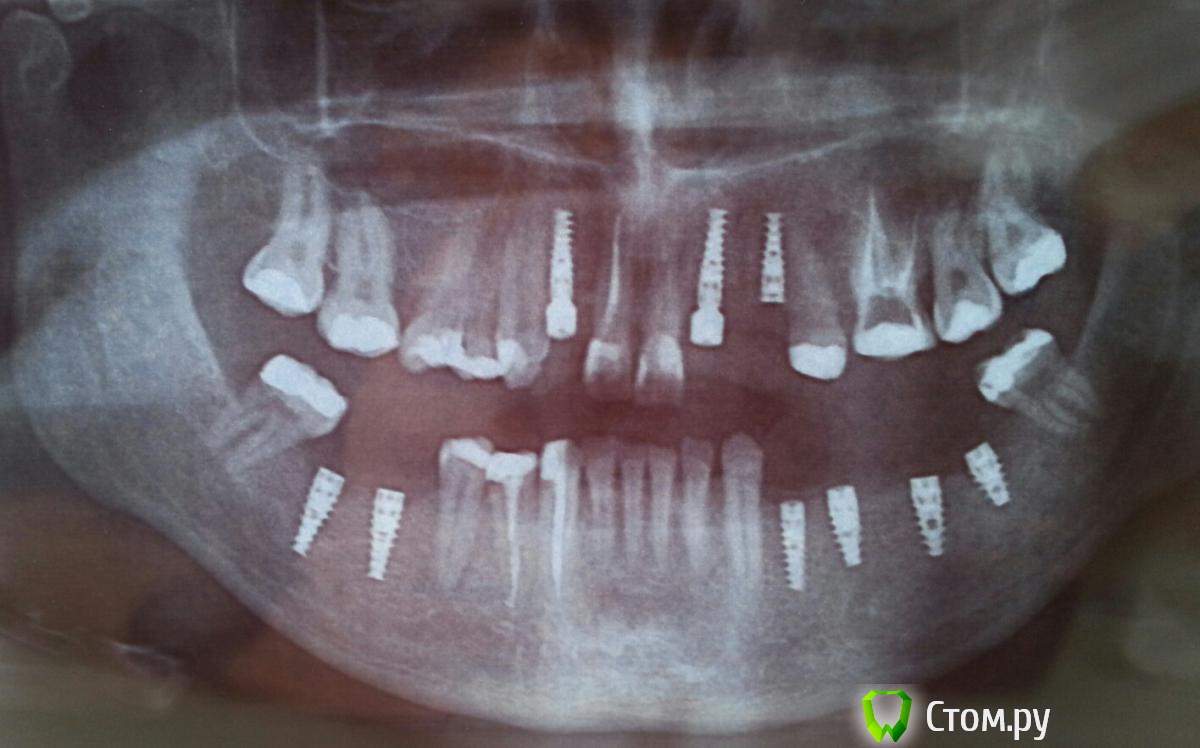

pandas17 Опубликовано 28 марта, 2014 Автор Поделиться Опубликовано 28 марта, 2014 Вот снимок.Надеюсь всё впорядке. 2 Ссылка на комментарий

pandas17 Опубликовано 28 марта, 2014 Автор Поделиться Опубликовано 28 марта, 2014 Наверху нехватаит высоты кости 22.23.12 поэтому поставили так. Ссылка на комментарий